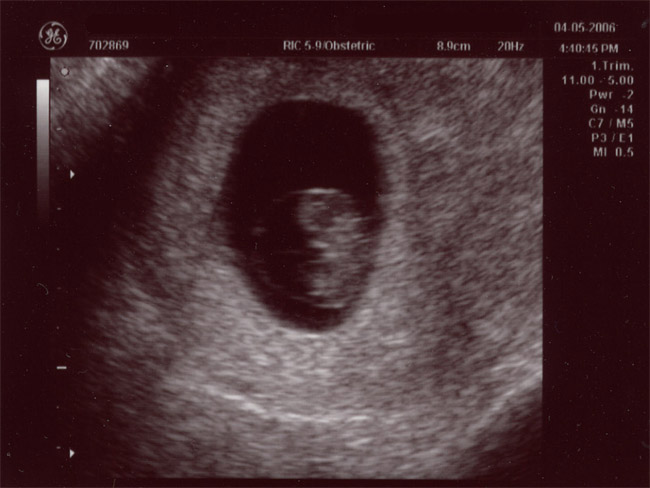

| April 5, 2006 - Eight Week Ultrasound (The First Pics of Baby Palermo!) |

| I was having some

spotting this morning and I was pretty worried. I immediately called

the doctor and they told me to come in around 1:30pm. It was pretty

tough to stay at work for a couple of hours before my appointment since I

really wasn't sure what was going on. When I got to the doctor's

office, they saw me right away and the doctor didn't seem too worried.

She did want to do an ultrasound just to be sure that little baby was

staying as cozy as possible in there. They did the ultrasound and

everything was just fine. The baby was measuring 4 days ahead of

schedule and I was so excited to see the baby moving all over the place.

Today, I got my official due date--November 15, 2006. YAY!!! ~Jen |